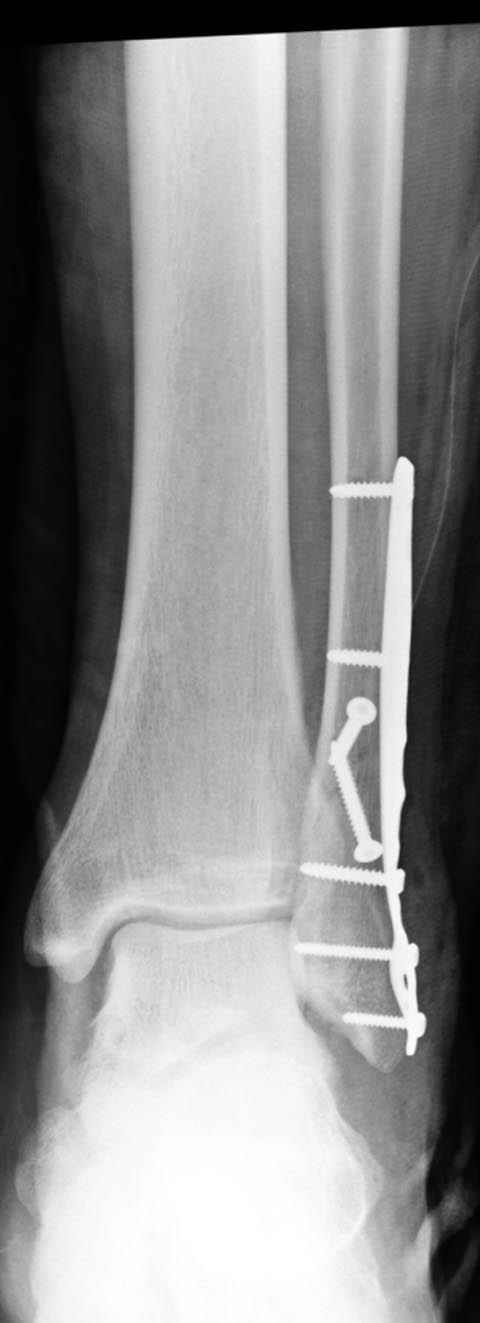

По снимку ваш случай относится к Weber В, фиксацию производят восстановлением длины малоберцовой кости, под ренгеном (ЭП)контролем, для этого я предпочел бы латеральный доступ, остеотомия по линии перелома, удлинение малоберцовой засчет скоса линии остеотомии, компрессия “lag technique”по линии остеотомии и фиксацию провести латеральной пластиной. Отдельный задний доступ, остеотомия по линии перелома, репозиция и фиксация заднего края вашим предпочтительным методом: 3.5мм шурупом с шайбой или пластиной Antiglide Butress

method. При восстановленном суставе, уменьшится медиальная щель, а при Weber В повреждается только передне-нижняя межберцовая связка синдесмоза, повреждение которой приводит к наружной ротации

малоберцовой, но после восстановления всех смещений, связка автоматический приближается к исходному и нет необходимости восстановления синдесмоза.